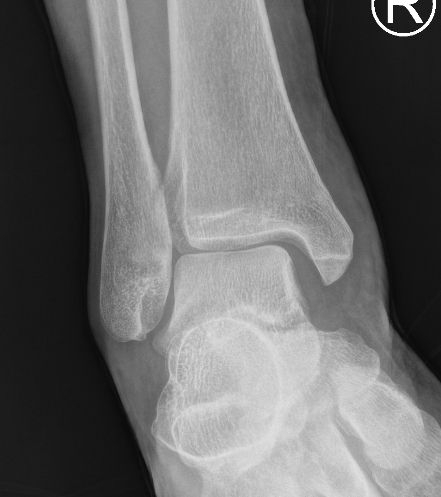

四級韌帶撕裂 (嚴重)

| 病徵: 四級踝關節扭傷屬於嚴重病例,韌帶斷裂,踝關節半脫位。症狀包括劇烈疼痛、腫脹、踝關節不穩定和行走困難。 |

| 腫痛 |

距骨移位 |

選擇1: 手法復位+石膏固定+短身步行靴(A16b)

「手法復位」後,需用石膏固定3週,並進行X光檢查以確保沒有半脫臼。之後,受傷的踝關節可繼續以石膏固定大約3週,靜止休養,促進癒合。隨後使用短身步行靴(A16)進行大約3週的復健治療,所有治療期間需使用拐杖,避免足踝負重所導致的疼痛及半脫臼,並在拐杖的輔助下進行階段性康復,漸進式負重。